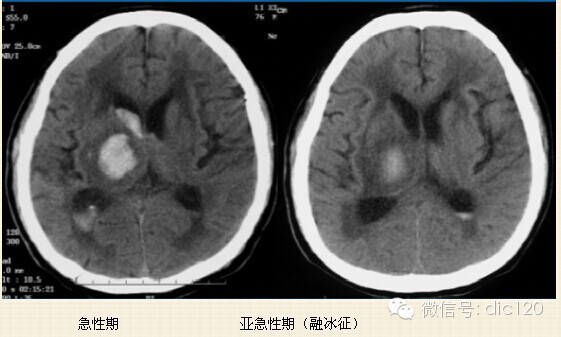

2.急性期(7-72小时):红细胞脱水萎缩,主要含有脱氧血红蛋白,此期灶周水肿,占位效应明显。

3.亚急性期(3天-2周):红细胞内主要为正铁血红蛋白,水肿及占位效应减轻。

在CT上对急性脑出血的定位准确 ,为高密度影像。